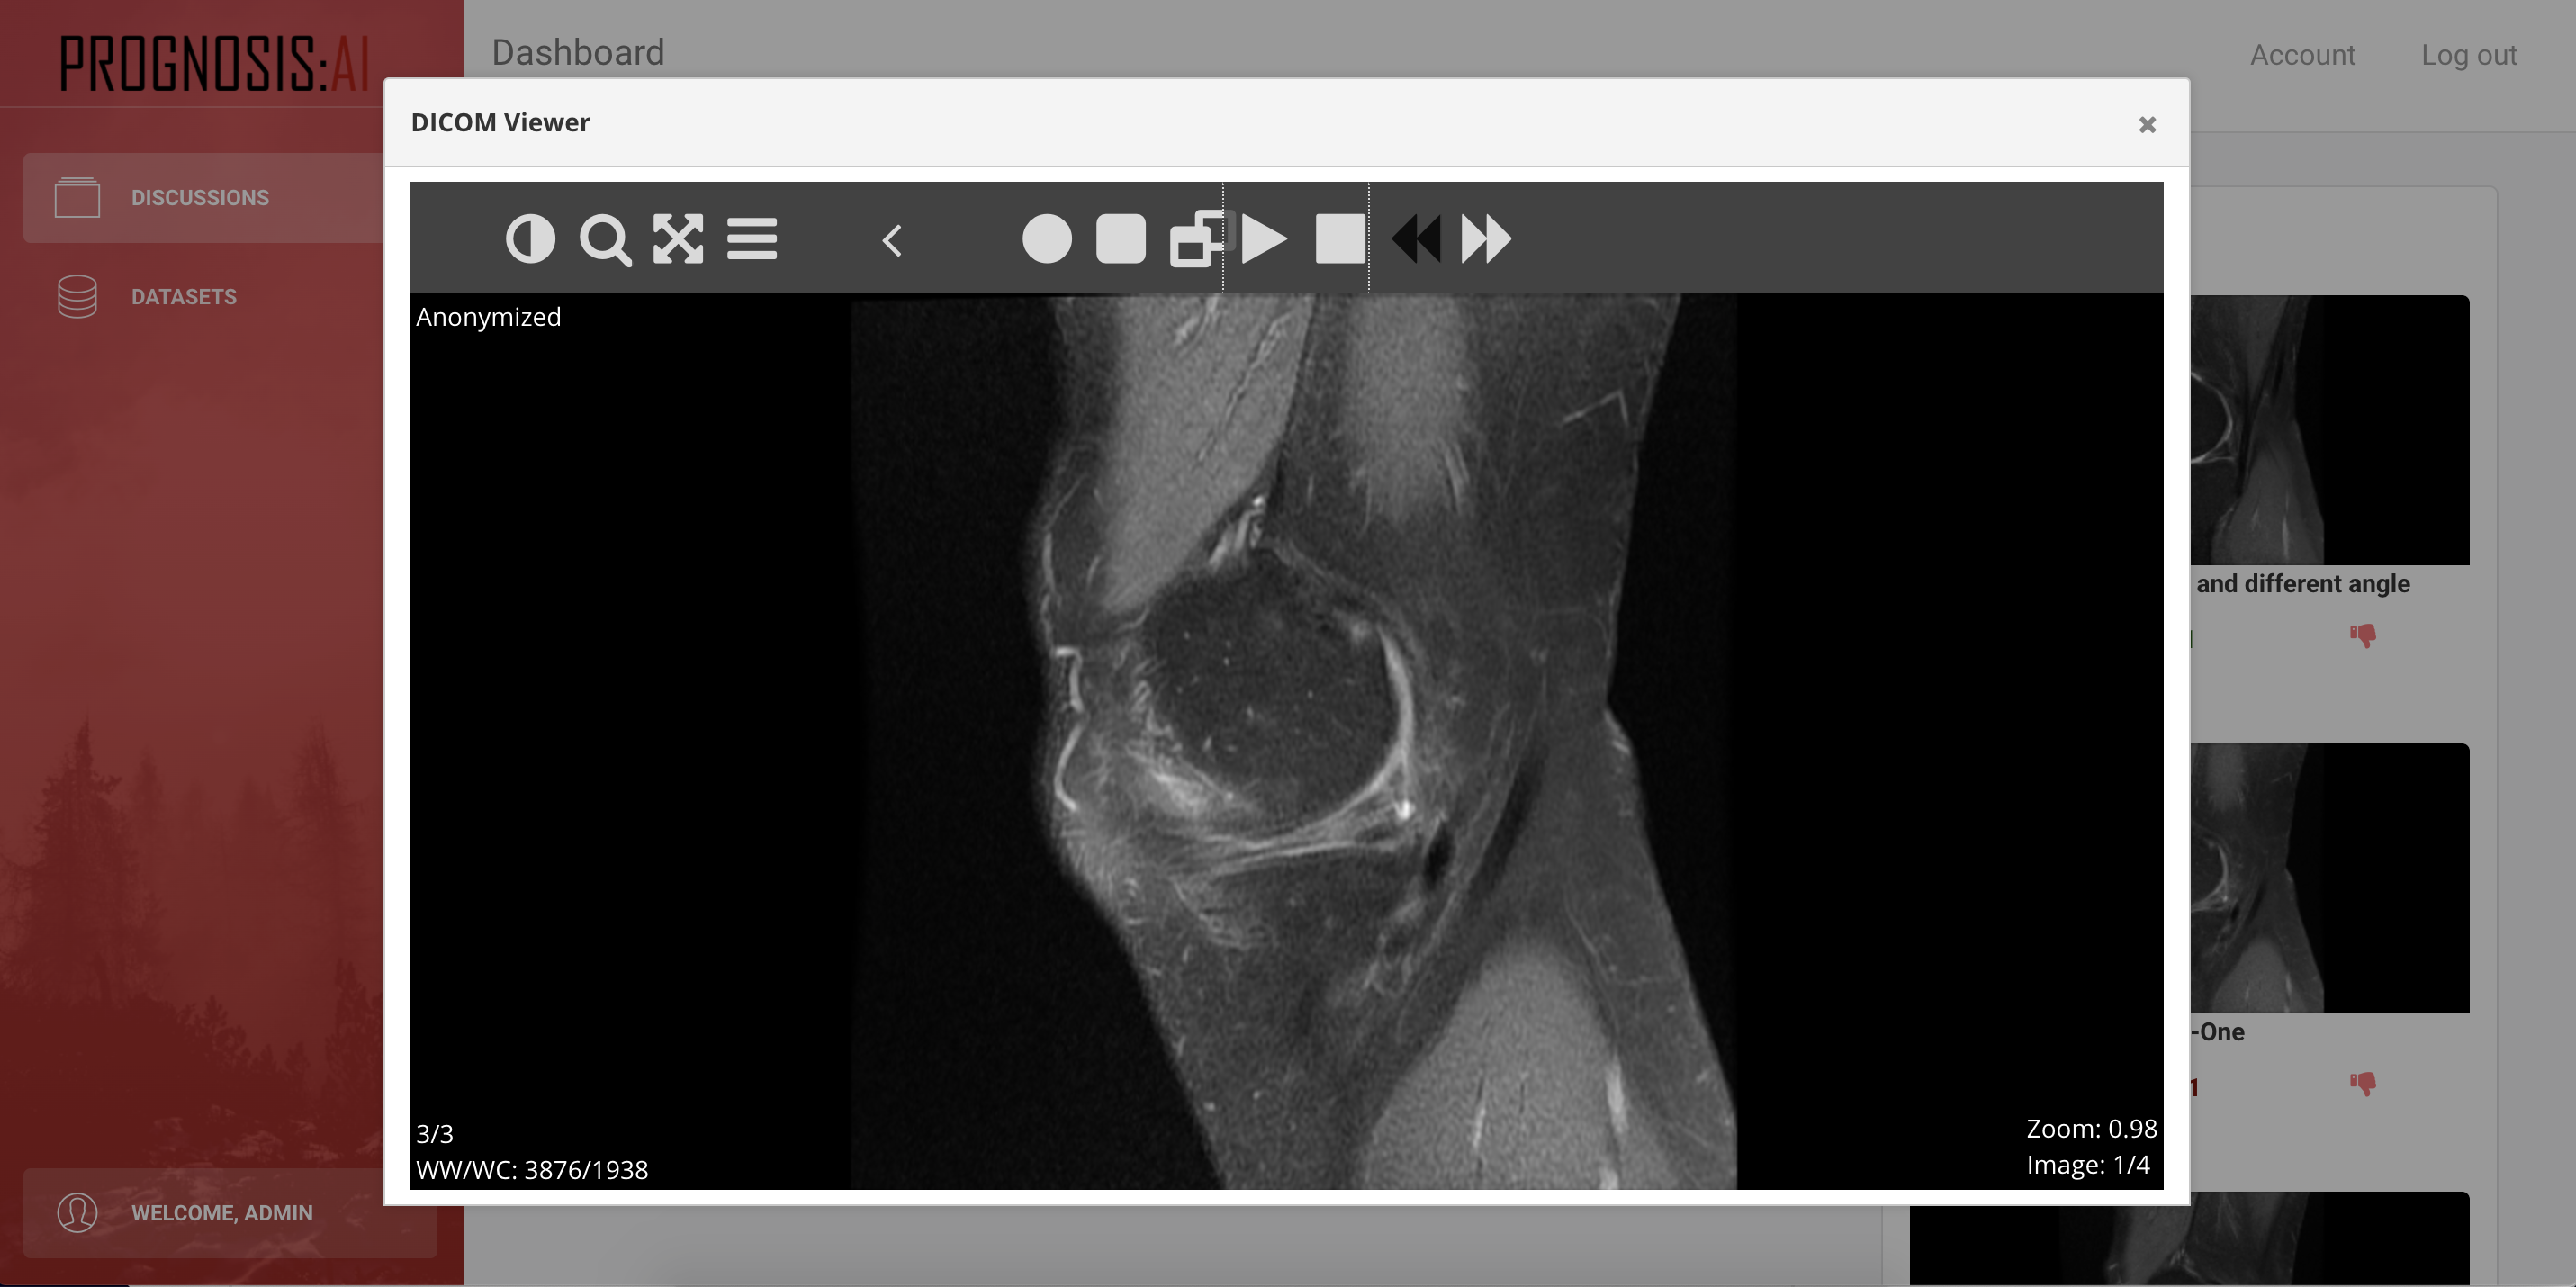

The PROGNOSIS:AI is an innovative and simple web-based AI Medical Image Analysis platform for medical professionals. The platform allows certified medical professionals to upload their patient’s images in a confidential manner and then be anonymously processed by our machine learning backend which will produce labels on the content of the image (e.g. automated interpretation of knee MRIs). Other forms of user-generated content will consist of the posts that the users make. The platform will also allow users to open a discussion on a given medical topic and to upload the respective images that they would like to have interpreted, and analyzed. Furthermore, these discussions then also become visible to other users of the PROGNOSIS:AI platform, upon which they are able to comment on the health issue and provide their own suggestions. The owner of the discussions is then able to close his or her discussion and use the information gathered through his post on this platform to conclude on a final decision making over the diagnosis in respect of patients’ images. On top of that experts will be able to download securely health datasets that could be used for diagnosis or prediction of unknown or little known health conditions. The datasets created will be labelled in order to be used for the prediction algorithms.

What started as an idea of a medical community powered sharing platform, turned into a much more impactful project. Medical data is very sensitive and comes in a wide variety of formats, all of which are exclusive to the field. From a technological perspective, the primary obstacle was the integration of support for the DICOM format. DICOM is a universally used image format in the medical field, used to store images of patients obtained using CT scans, MRI machines, Xray and other technologies. Secondly, the necessary steps had to be taken to ensure the web-application offers end-to-end encrypted traffic. This ensures that no uninvited third parties can organize dangerous man-in-the-middle attacks. From a legal perspective, we had to consider a variety of data protection laws, both on the level of EU and individual countries. For this reason, the solution prototype is entirely hosted in the EU region, and any further expansion will carefully consider any regulatory data requirements.